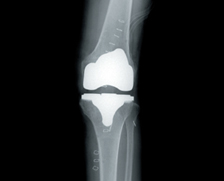

CUVIS-joint is a cutting-edge surgical robot system that improves the completion of artificial joint surgery with optimal surgical planning and precise cutting.

With Optimal tracking sensors and self-developed surgical planning CUVIS-joint helps patients that are in need of artificial knee surgery.

What’s as important as the precise surgical plan is to select and insert the personalized artificial joint. The doctor uses the robot to select the artificial joint for the patient and insert it accurately.

CUREXO’s robotic artificial joint surgery system provides the correct alignment of a patient’s leg axis with the submillimeter dimensional accuracy and precise cutting for the optimal surgical outcome.

Insert and fix the implant decided and finished the surgery.